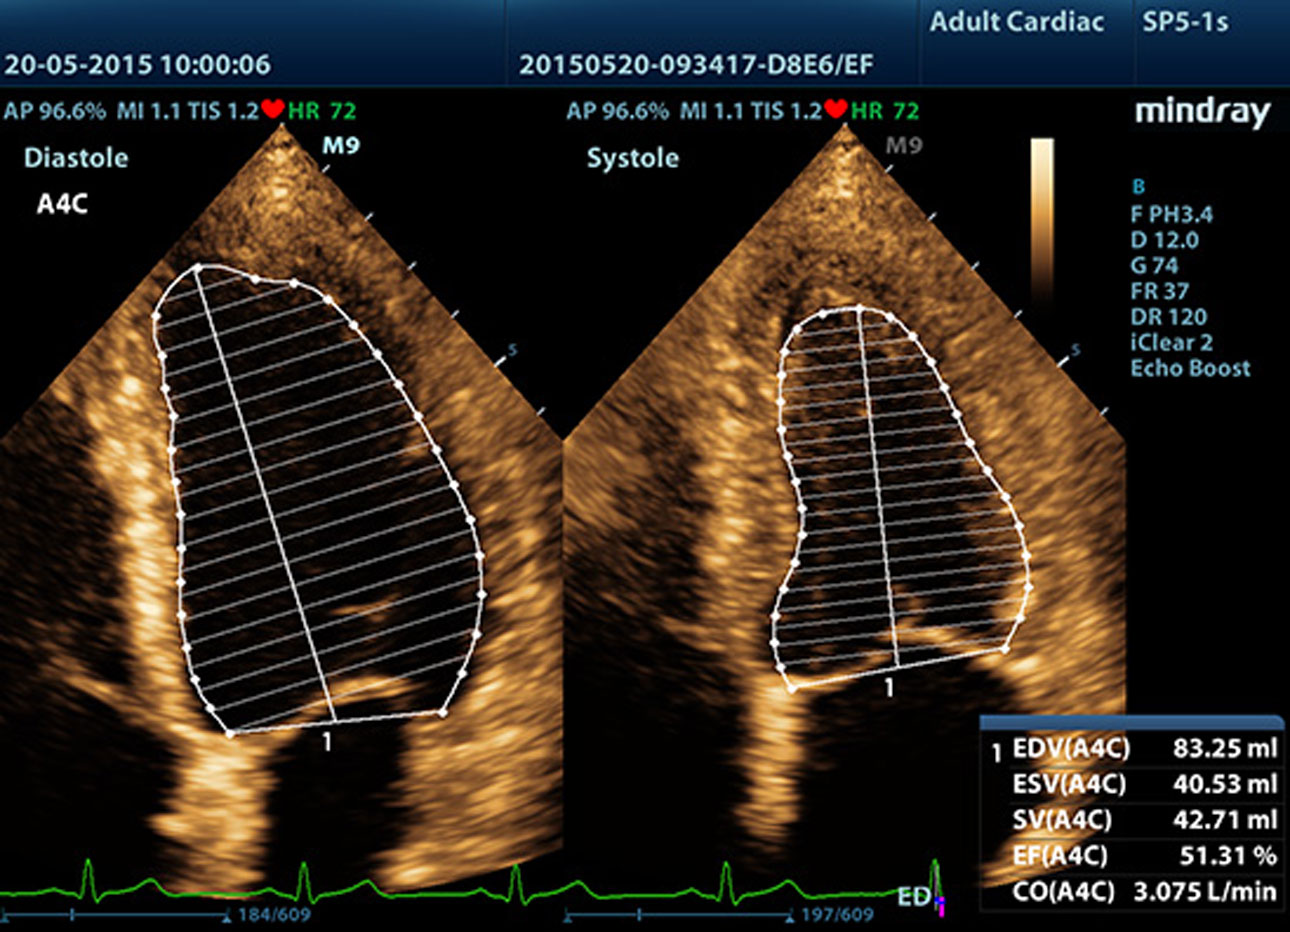

AutoEF

Automatic recognition of the diastole and systole from 2D echo clips and output EDV/ESV/EF etc. results using the Simpson method.?